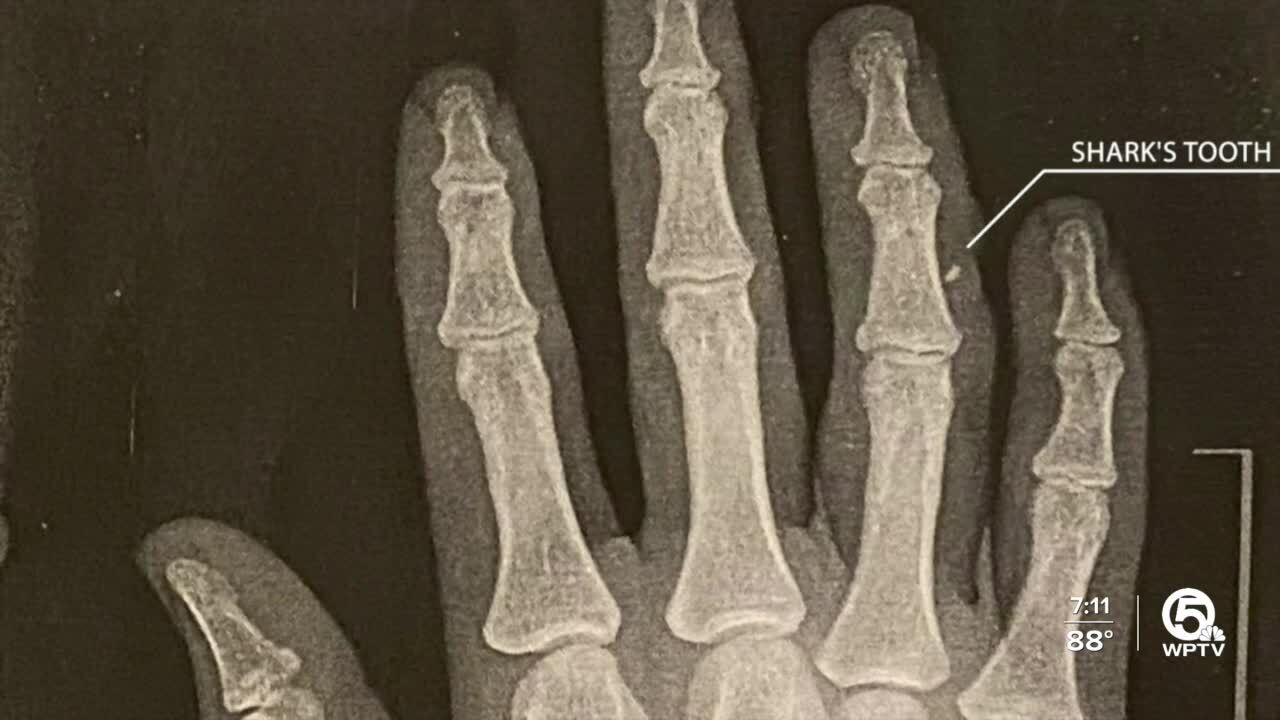

An X-ray of her hand showed there is a silver lining.

Doctors found a fragment of the shark's tooth in her ring finger. It's a keepsake of a weekend that will be impossible to forget.